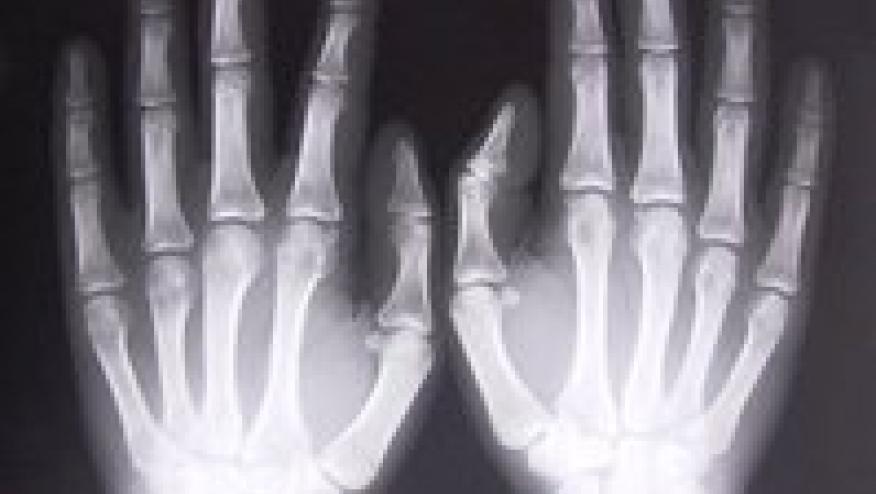

Healthy Bones Formed During Adolescence Save

An article in the Journal of Bone and Mineral Research reports that physical activity during adolescence is an important determinant in bone strength. (Citation source http://buff.ly/2oph6vO)

Moderate to vigorous physical activity was a positive independent predictor of bone strength and cortical porosity. Conversely, sedentary time or physical inactivity can lead to weaker bones in teenagers.

Between the ages of 10 to 14 for girls and 12 to 16 for boys, up to 36 percent of the skeleton is formed.